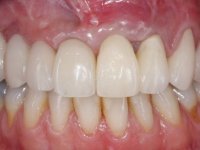

The provisional FPD were placed in the maxilla and were used to remodel soft-tissue architecture and test the aesthetic concept achieved with the diagnostic wax-up.

In the end of the last appointment, the treatment was considered fully integrated, concerning function and aesthetics, and the patient was satisfied.